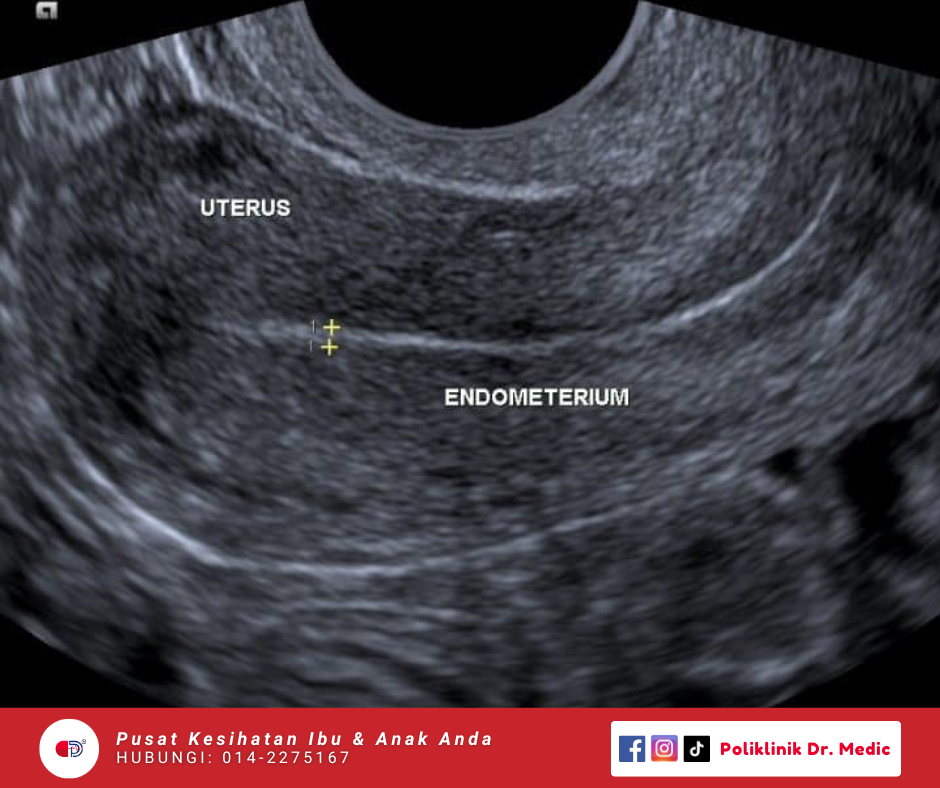

Female Pelvis Scan

Ultrasound Pelvis sesuai untuk wanita. Pemeriksaan untuk tengok keadaan rahim, ovari dan kawasan pelvis. Sesuai untuk kesan masalah haid, ketulan, cyst, atau isu kesuburan.

RM99